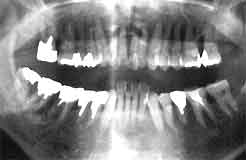

| 初診時 パノラマ | 7年後 パノラマ |

| 歯槽骨吸収は中程度 53歳 女性 |

骨吸収は抑制され喪失歯もない |

初診時口腔内およびX線所見:

口腔清掃状態は比較的良好で、全体に軽度〜中程度、下顎前歯部では1/2以上(重度)の

歯槽骨吸収を認める。